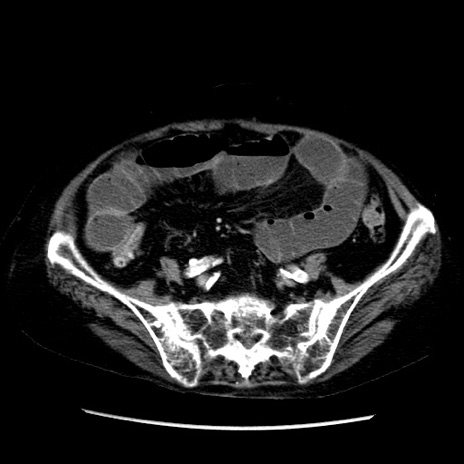

症例14(横断像)

【症例】 90歳代女性

【主訴】 腹痛・嘔吐

【現病歴】今朝から左側腹部痛を認めた。 経過観察していたが、嘔吐を認めたため来院。

【既往歴】 子宮癌術後

【身体所見】 意識清明、BP 127/54mmHg、P 98bpm Sp02 95%(RA)、BT 35.8°C、腹部平坦・軟腸ぜん動音聴取良好、右下腹部圧痛(+) 反跳痛なし

【データ】WBC 9800、CRP 0.46